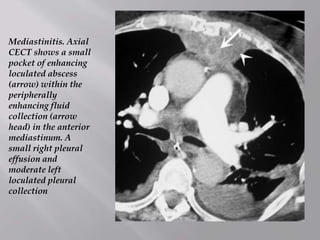

 This is a rare but serious condition due to acute

infection of the mediastinum. Chest CT is the

best imaging modality of choice, which aids the

diagnosis and guides percutaneous drainage of

the mediastinal collection.

 Causes include esophageal/pharyngeal

perforation, post-sternotomy, extension of

infection from elsewhere and may be

associated with empyema

Mediastinitis. Axial

CECT shows a small

pocket of enhancing

loculated abscess

(arrow) within the

peripherally

enhancing fluid

collection (arrow

head) in the anterior

mediastinum. A

small right pleural

effusion and

moderate left

loculated pleural

collection